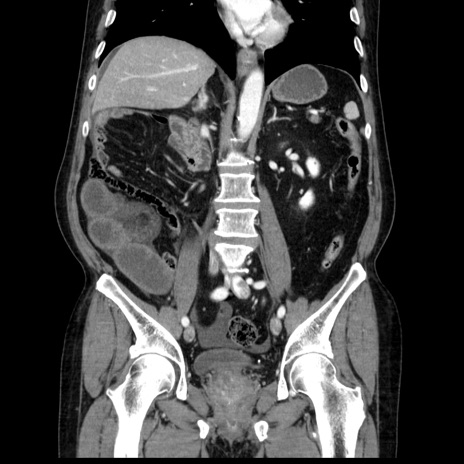

横断像

【症例】80歳代男性

【主訴】臍周囲痛

【現病歴】約6時間前から臍下部痛が出現。次第に腹部膨隆・背部痛も生じてきたため来院。背部痛の場所は変化しない。

【身体所見】意識清明、BT 36.3℃、BP  131/87mmHg、P 87bpm、SpO2 100%(RA)、臍周囲自発痛・圧痛あり、反跳痛なし、自発痛部位に一致して板状硬あり、腹部膨隆、腸雑音減弱、CVA tenderness両側陰性。

【データ】WBC 19600、CRP 0.33